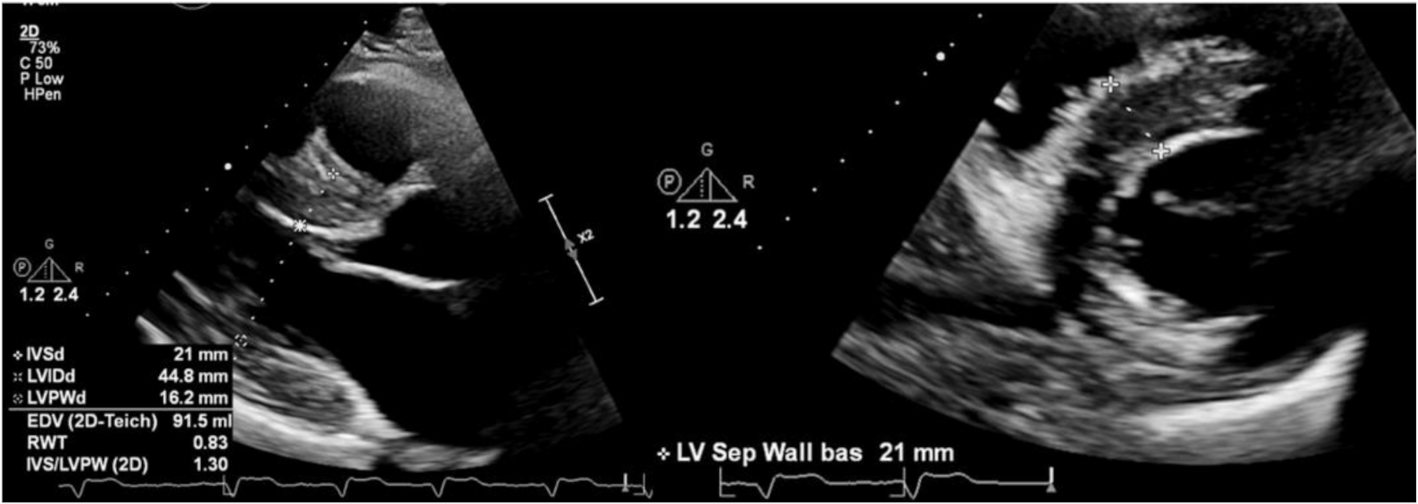

2. Diagnosis: Maximal Wall Thickness and LV Hypertrophy

2.1. Transthoracic Echocardiography